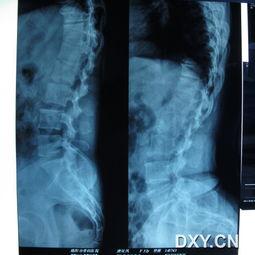

首先,让我们来了解一下脊柱弯曲。脊柱弯曲,医学上称为脊柱侧弯,是指脊柱在X光片上呈现的侧弯或后凸。这种弯曲不仅影响外观,还可能引起疼痛、呼吸困难等问题。据统计,全球约有5%的成年人患有脊柱弯曲。